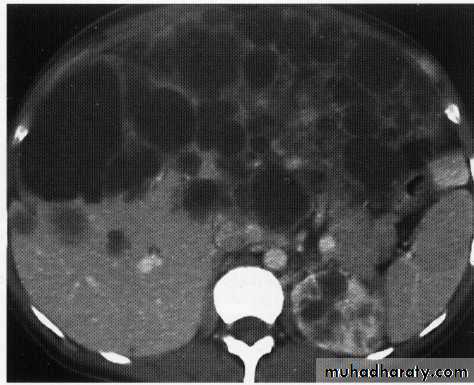

hepatic mets

hepatic mets,arterial phase

hepatic mets venous phase